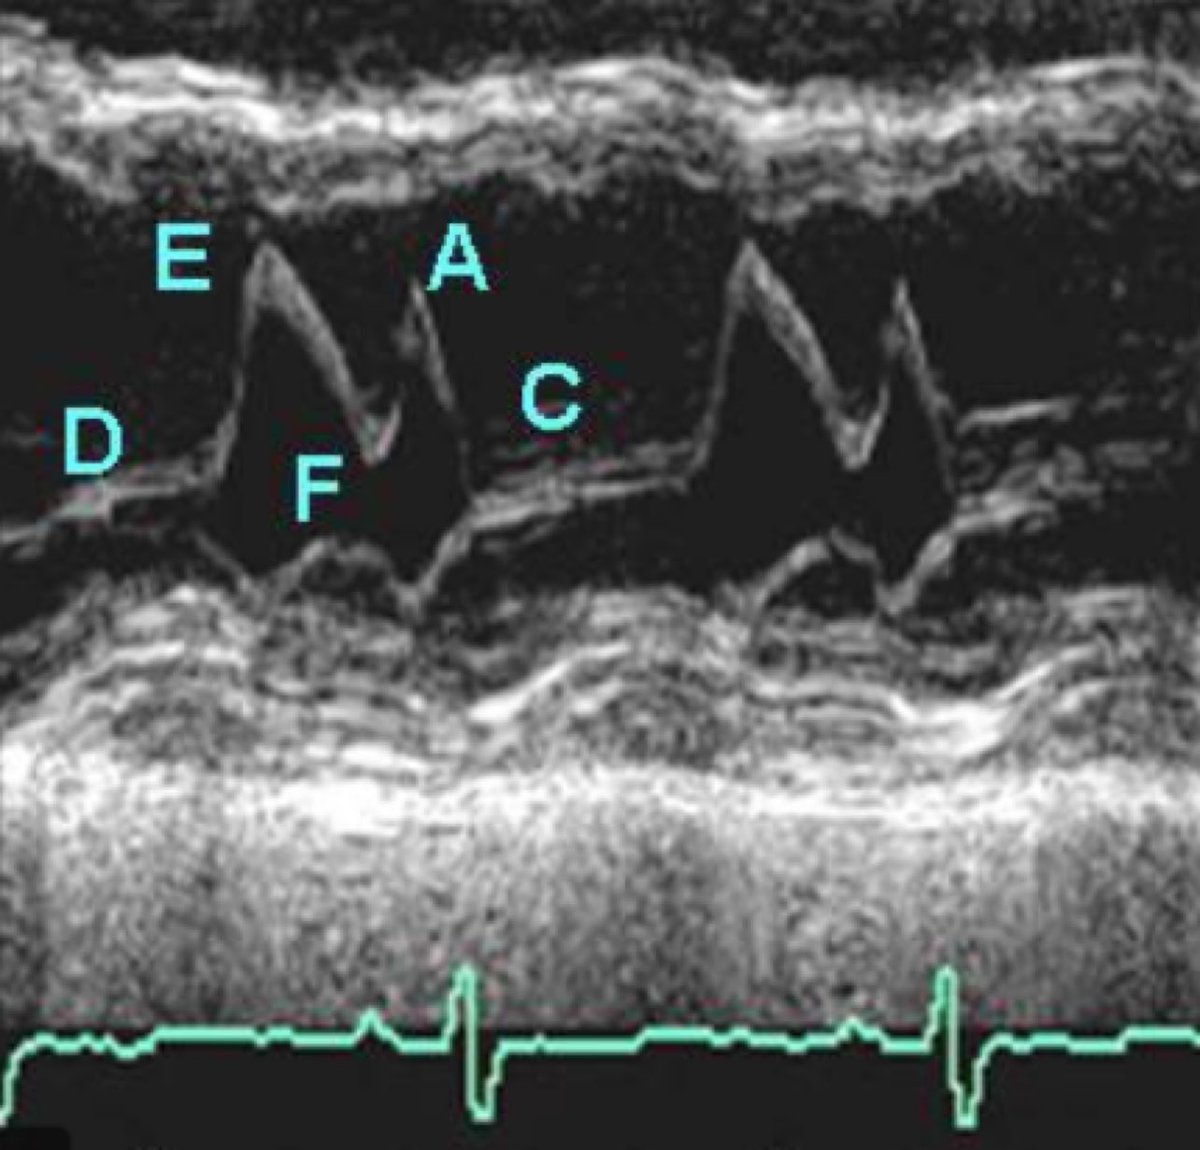

Anterior Mitral Valve M-mode points for #firstecho D: End systole E: Early opening F: Mid-diastolic Closure A: Atrial Systole C: Closure

Arafatmahmoud's tweet image. Anterior Mitral Valve M-mode points for

#firstecho

D: End systole

E: Early opening

F: Mid-diastolic Closure

A: Atrial Systole

C: Closure